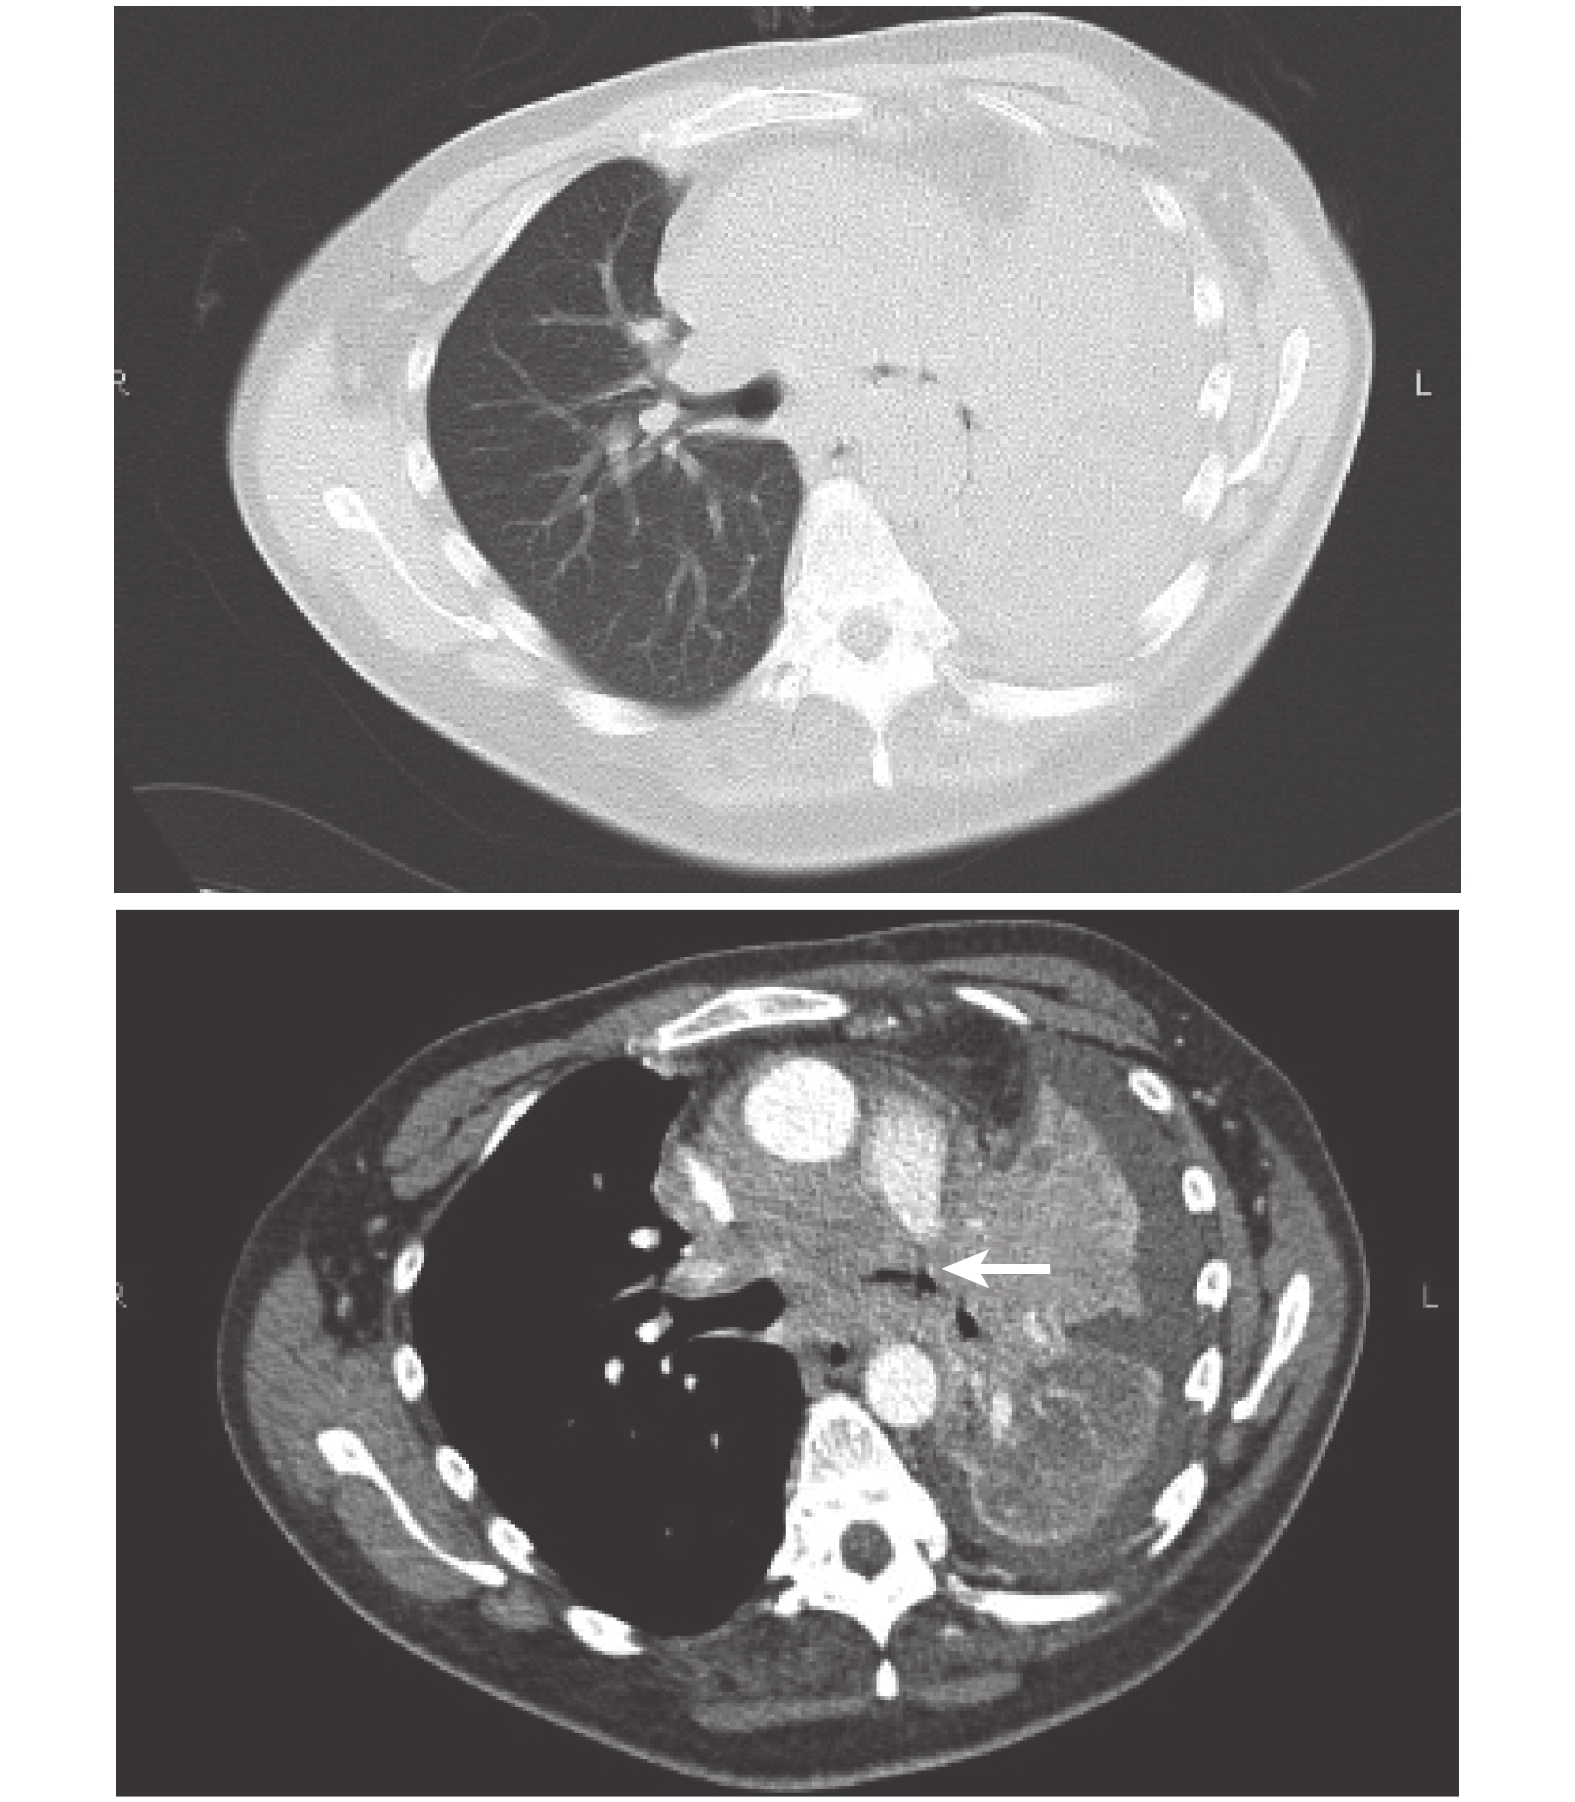

患者,男,36 歲。因“發熱伴咳嗽、咳痰、活動后氣促 1 個月余”入院。既往有強直性脊柱炎病史 12 年,藥物治療控制病情穩定。否認吸煙史和腫瘤家族史。入院查體:體溫 38 ℃,呼吸 20 次/min,脈搏 124 次/min,血壓 120/80 mm Hg(1 mm Hg=0.133 kPa)。神志清晰,呼吸平穩。全身皮膚未及黃染,無瘀點、瘀斑。淺表淋巴結未及腫大。右肺呼吸音稍粗,左肺呼吸音低,未及明顯干濕性啰音。心率 124 次/min,律齊,心音有力。腹平軟,無壓痛、反跳痛及肌衛,肝脾肋下未觸及,雙下肢無浮腫。脊柱后凸強直性固定。神經系統查體未發現明顯異常。血常規:C 反應蛋白 160 mg/L,白細胞計數 15.4×109/L,中性粒細胞百分比 87.6%,D-二聚體 0.64 mg/L,肝腎功能正常,白蛋白 28.0 g/L,肌酸激酶同工酶 42.00 U/L,a-羥丁酸脫氫酶 749 U/L,乳酸脫氫酶 1 138 U/L,N 端腦鈉肽前體 214.50 pg/ml,肌鈣蛋白 I 0.020 ng/ml,降鈣素原 0.18 ng/ml,甲胎蛋白 2.07 ng/ml,癌胚抗原 0.49 ng/ml,糖類抗原 CA19-9 8.27 U/ml,糖類抗原 CA125 188.40 U/ml,糖類抗原 CA15-3 20.64 U/ml,糖類抗原 CA724 0.97 U/ml,糖類抗原 CA211 132.40 ng/ml,神經烯醇化酶 14.45 μg/L,鱗狀細胞癌抗原 0.60 ng/ml,免疫球蛋白 E 22.80 IU/ml,EB 病毒(Epstein-Barr virus,EBV)早期抗原(early antigen,EA)113 U/ml,EBV 核抗原(nuclear antigen,NA)>600 U/ml,EBV DNA(+)。淋巴結超聲檢查:雙側頸部多發淋巴結腫大,結構消失,部分相互融合,雙側鎖骨上淋巴結異常腫大,后腹膜、雙側頸部、腋窩、腹股溝未見明顯異常腫大淋巴結。電子支氣管鏡檢查:左主支氣管內新生物將管腔基本阻塞。鼻竇部增強 CT 檢查:鼻咽部 CT 掃描未見明顯異常。肺動脈血管造影檢查:左肺上葉占位可能,左側氣管及其分叉管壁欠均勻、管腔狹窄,縱隔淋巴結腫大,左肺下葉炎癥,左側胸腔積液,心包積液。CT 血管造影示左肺動脈變細,分支顯示不清(圖 1)。上腹部增強 CT 檢查:肝內多發轉移,腹水(圖 2)。肺通氣灌注掃描檢查:左肺通氣功能與血流灌注均極差;右肺通氣及血流灌注均未見異常。雙側下肢深靜脈彩超檢查:管腔內血流通暢,未見栓塞表現。心臟彩超:心包積液極少量,肺動脈稍增寬,左心室收縮功能正常。患者因強直性脊柱炎無法平臥,呈強迫體位,無法耐受鼻咽鏡、正電子發射計算機斷層顯像、骨掃描、頭顱磁共振等檢查評估病情。支氣管鏡活檢病理提示巢狀腫瘤細胞,細胞核呈空泡狀,腫瘤間質有淋巴細胞浸潤,原位雜交檢測 EBV 編碼小核 RNA(EBV-encoded small nuclear RNA,EBER)陽性(圖 3),經鼻竇增強 CT 排除鼻咽癌后明確診斷為原發性 PLELC。給予泰素帝聯合奈達鉑(TP)方案化療 2 次后患者臨床癥狀明顯改善,血白蛋白水平恢復正常,乳酸脫氫酶降低,復查胸部 CT 顯示左肺不張好轉,肺內腫塊明顯縮小(圖 4a、4b),后又給予患者 TP 方案化療 4 次,化療療效評估為病情穩定(stable disease,SD)(圖 4c、4d)。但化療結束后 1 個月患者再次出現胸悶氣促癥狀加重,胸部增強 CT 提示大量心包積液、胸腔積液,左肺病灶較前進展(圖 4e~4h)。患者無法耐受化療,僅接受對癥支持治療,最終死亡。